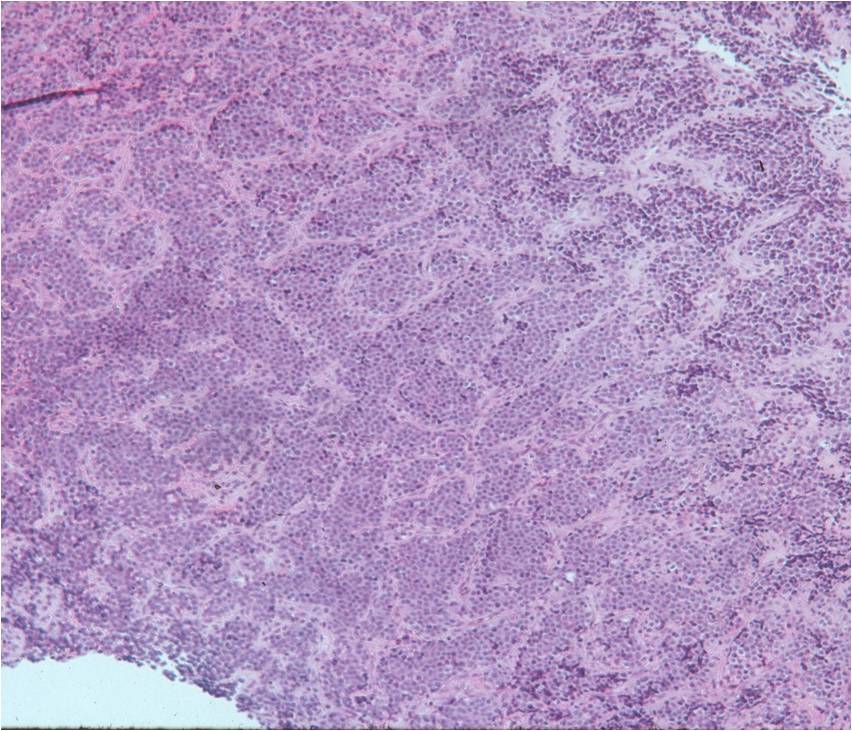

- Ewing sarcoma is composed of undifferentiated, small round, polygonal mesenchymal cells rich in glycogen

- Sheets of uniform cells with scanty pale cytoplasm and indistinct cell boarders

- No Matrix

- Nuclei are round/oval with finely dispersed chromatin

- Virtually no cytoplasm

- Areas of necrosis

- Variable number of mitoses

- Cells are similar in appearance

- Geographic necrosis with perivascular sparing

Small Round Blue Cells No Matrix Large Nuclei No Cytoplasm